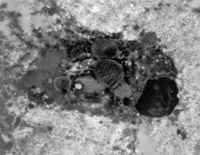

2. 電鏡觀察 受傷當(dāng)日上皮組織變性壞死,可見單核細(xì)胞核偏移、固縮,并有吞噬現(xiàn)象(圖5-3-12)。

5-3-12 燒傷當(dāng)日,單核細(xì)胞核偏移,固縮,并有吞噬現(xiàn)象  TE×8000